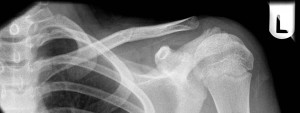

Medial and Lateral Third Fractures

Lateral third clavicle fracture